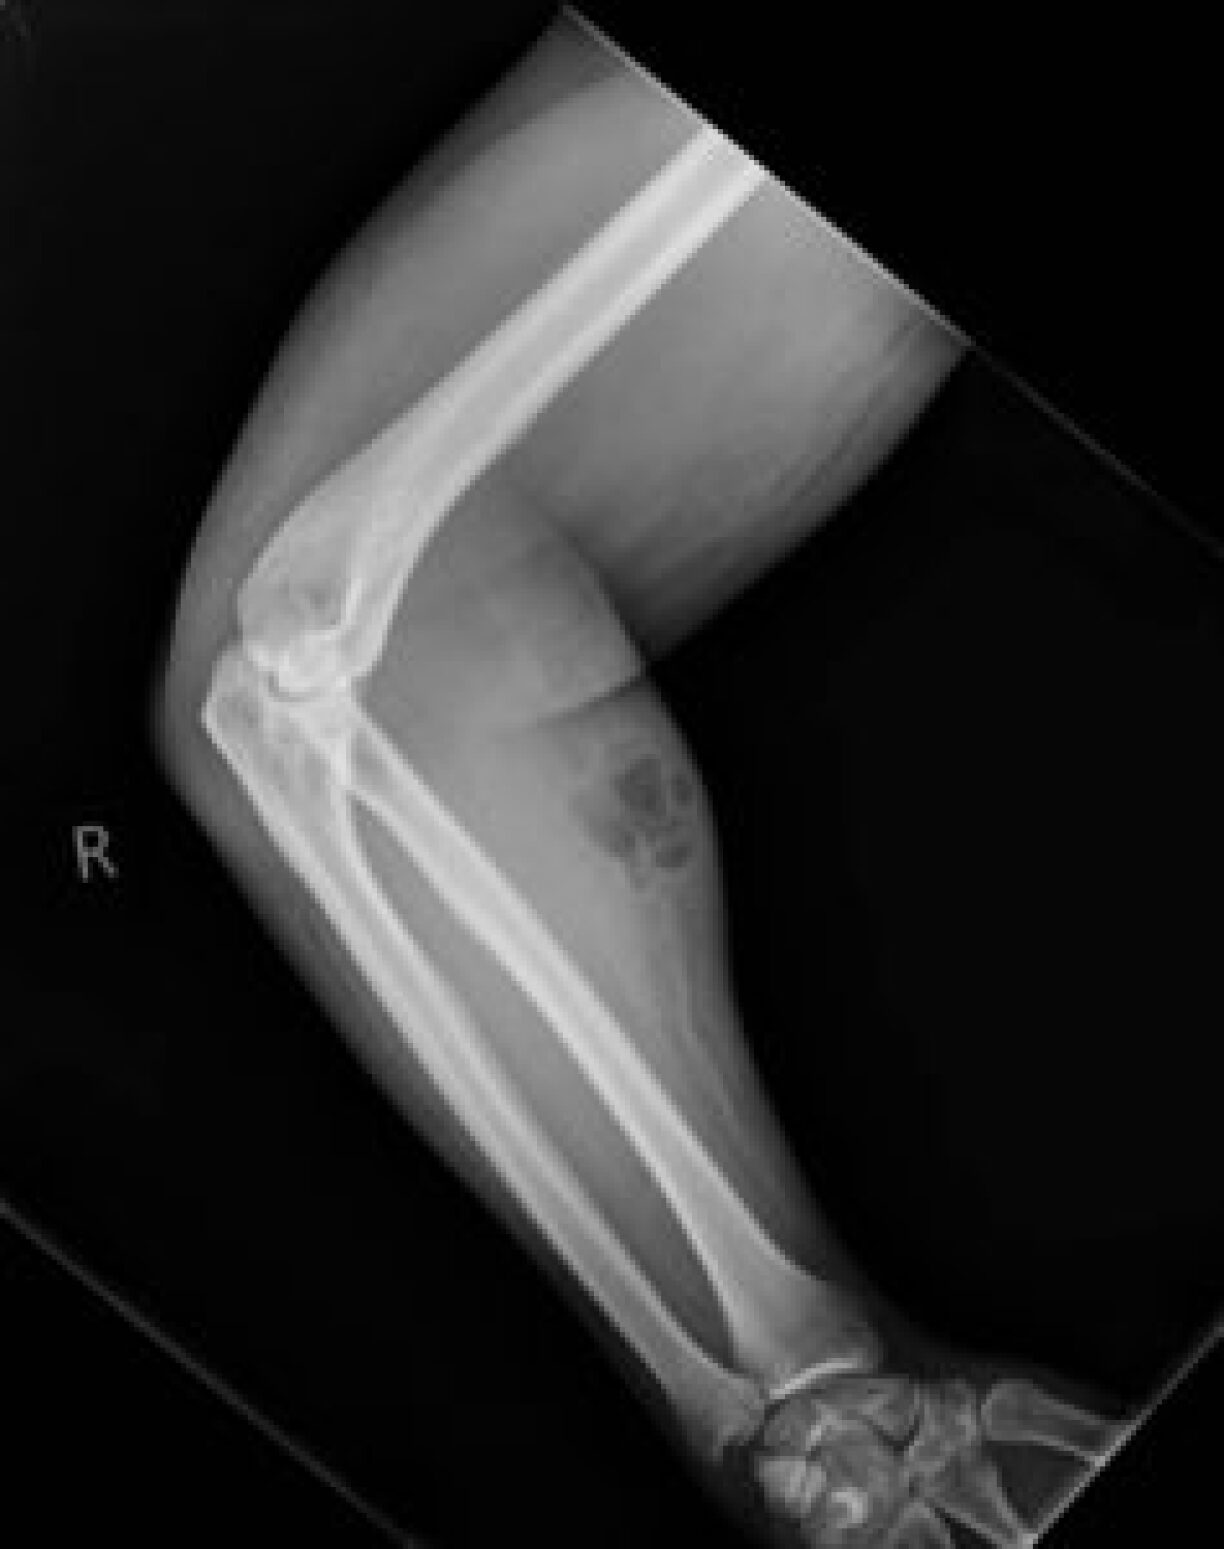

D’Suite vu senger Eegen-Therapie: Eng bakteriell Infektioun am Aarm, respektiv en Abzess, deen un der grousser, rouder Schwellung och net z’iwwersinn ass.